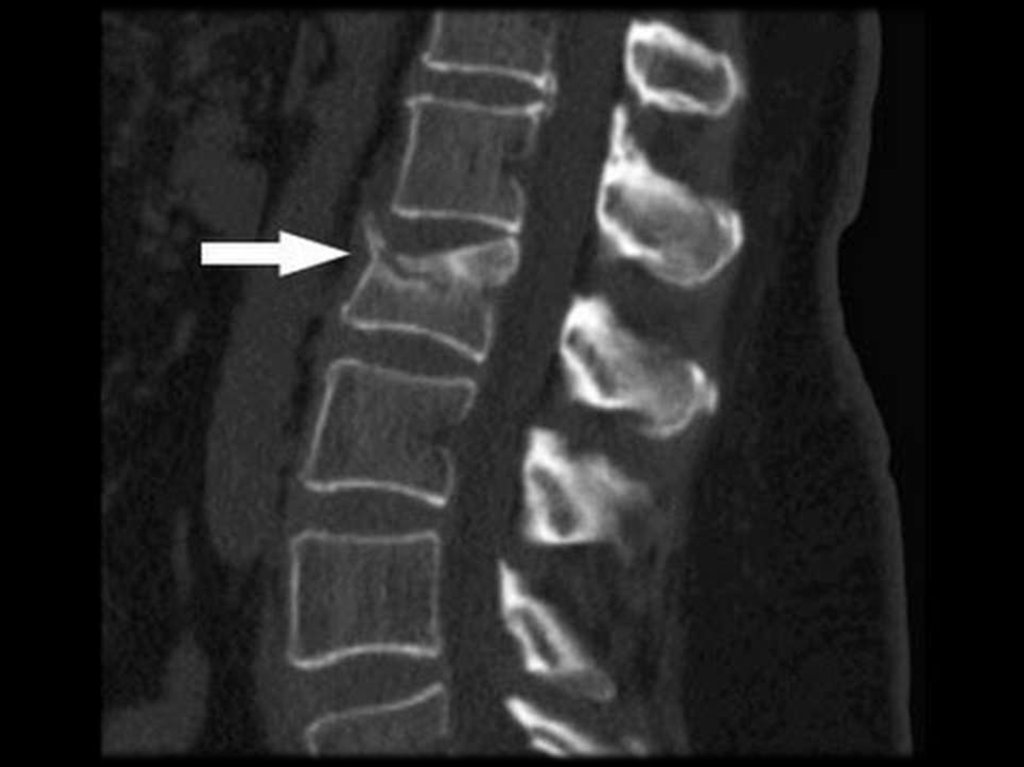

R-признаки при ОП (R-графия позвонков в

боковой проекции), потеря костной массы

при этом составляет 20 – 30%.

разряжение губчатой кости;

уменьшение количества трабекул на

единицу плотности кости;

повышенная прозрачность тел позвонков;

видны вертикальные трабекулы;

“рамочная” структура

тел

позвонков

(истончение и резкая подчёркнутость

контуров кортикального слоя кости при

разряжении

плотности

кости

тела

позвонка);

деформация тел позвонков

Виды деформации тел позвонков:

передняя клиновидная;

задняя клиновидная;

двояковогнутая деформация (по типу

“рыбьих”);

компрессионная деформация;

сочетанная.